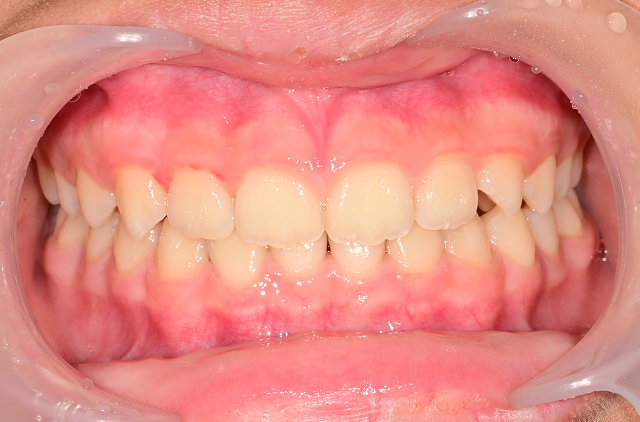

턱 성장 방향과 교합을 조기에 바로잡아

평생 바른 치열과 얼굴 균형을 만듭니다.